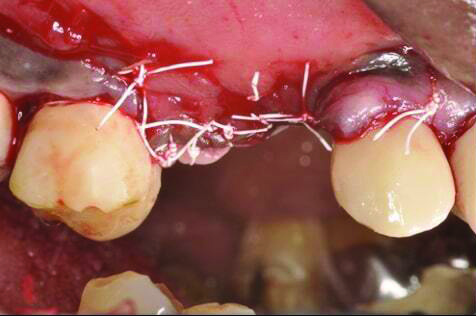

Fig 3 and Fig 4. Case 2: Initial clinical presentation showing implant No. 6 with RPI, having been impacted by fractured tooth No. 5 (Fig 3); radiograph showing fractured tooth No. 5 with periapical lesion extending to the distal aspect of implant No. 6 (Fig 4).

Figure 3

Fig 4. Case 2: Initial clinical presentation showing implant No. 6 with RPI, having been impacted by fractured tooth No. 5 (Fig 3); radiograph showing fractured tooth No. 5 with periapical lesion extending to the distal aspect of implant No. 6 (Fig 4).

Patient 2: A 63-year-old healthy male patient presented with implant No. 6 exhibiting RPI, having been affected by previously endodontically treated and fractured tooth No. 5 (Figure 3 and Figure 4). The implant had probing depths ranging from 4 mm to 10 mm (Table 1) with the most severe bone loss at the distal aspect of implant No. 6 (Figure 3 and Figure 4).